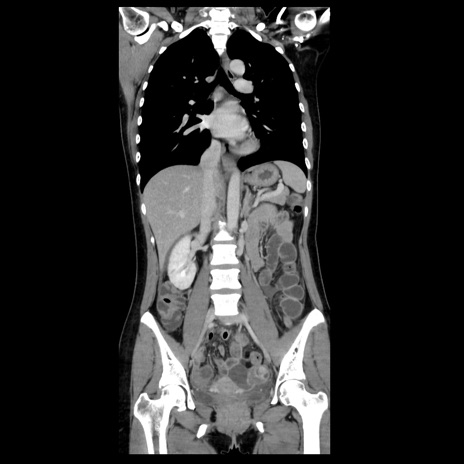

症例39(冠状断像)

【症例】40歳代女性

【主訴】上下腹部痛

【現病歴】2日目から下腹部痛あり。夜間は痛みで眠れなかった。昨日より上腹部痛と下痢が出現。臥位で痛みは軽快したため、休んでいた。本日になって臥位でも立位でも痛みが強くなってきたため救急要請。

【既往歴】子宮内膜症

【身体所見】部:平坦・軟、左上下腹部に圧痛あり、反跳痛あり。

【データ】WBC 21800、CRP 26.78

CT